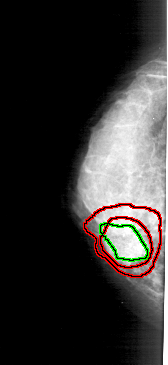

A_1212_1.LEFT_MLO

FILE: A_1212_1.LEFT_MLO.OVERLAY

TOTAL_ABNORMALITIES 2

ABNORMALITY 1

LESION_TYPE MASS SHAPE IRREGULAR MARGINS SPICULATED

ASSESSMENT 5

SUBTLETY 5

PATHOLOGY MALIGNANT

TOTAL_OUTLINES 1

BOUNDARY